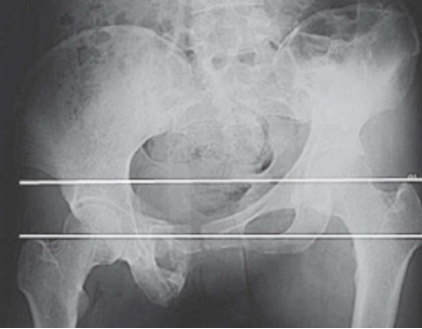

(2)陈旧性骶髂关节骨折脱位的治疗:此类损伤处理困难。因为骨痂多、粘连重、手术时出血多、复位困难。手术治疗是针对明显的遗留症状,如负重时的放射性神经痛、行走痛、步态明显异常、下肢不等长。对于神经症状,一般采用神经营养药物等非手术治疗,当有影像学证据表明神经受到卡压时,可以实行前路神经探查松解术。如果骶髂关节陈旧脱位、骨盆倾斜导致下肢不等长,可以根据具体情况采取肢体短缩术、肢体延长术、髋骨截骨术,或者畸形愈合处截骨术等方法进行治疗。如下图所示,一位女性患者因车祸致脑外伤及C3型骨盆骨折,4个月后就诊时骨盆骨折已畸形愈合,肢体不等长达6 cm。骨盆前后位X线片显示左侧髂骨明显上移,使双侧大粗隆不在同一水平(图1)。

图1(图源:作者提供)